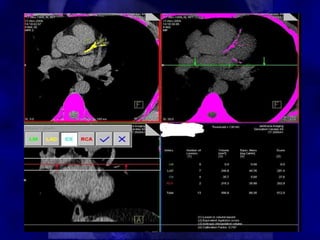

• Computed tomography allows

Computed tomography allows

quantification of this calcium.

• The method is based on the maximum x-ray

attenuation coefficient, or CT number

(measured in Hounsfield units [HU]), and

the area of calcium deposits.

• First, calcified lesions are identified on CT

images by applying a threshold of 130 HU

to the entire image set; tissues with

densities equal to or greater than the

threshold are considered to correspond to

calcium.

• For each coronary artery, i, a region of

interest (ROI) is drawn around each

calcified lesion, j.

• The maximum CT number, CTmax ij , of

the ROI is determined and used to assign

a weighting factor, wij.

• The area, Aij, of the ROI is also

determined.

• The Agatston score, Sij, is computed as

the product of the weighting factor and

the area:

Sij = wij x Aij

Where :

• w ij = 1 if CTijmax 130 - 199 HU

2 if CTijmax 200 - 299 HU

3 if CTijmax 300 - 399 HU

4 if CTijmax > 400 HU

• The score for all lesions in all coronary

arteries is summed to determine the total

calcium burden:

Stot =  Sij